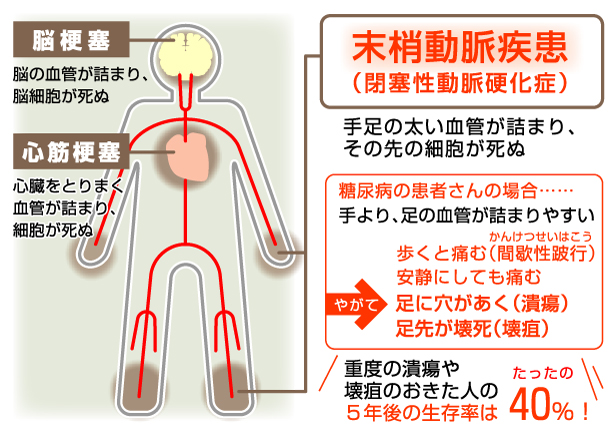

末梢血管疾患 (PVD) は、心臓や脳の外側の血管に問題がある一連の状態です。末梢動脈疾患 (PAD) は、動脈が狭くなったり閉塞したりする PVD の一種です。

PAD は、特に、酸素を含んだ血液を心臓から運び出す血管である動脈に関係する疾患を指します。

PADの主な原因はアテローム性動脈硬化です。アテローム性動脈硬化症は、動脈内のプラークの蓄積です。

PADの原因

アテローム性動脈硬化症は、プラークの蓄積によって動脈が狭くなる病気です。

PAD およびアテローム性動脈硬化症の危険因子には次のものがあります。